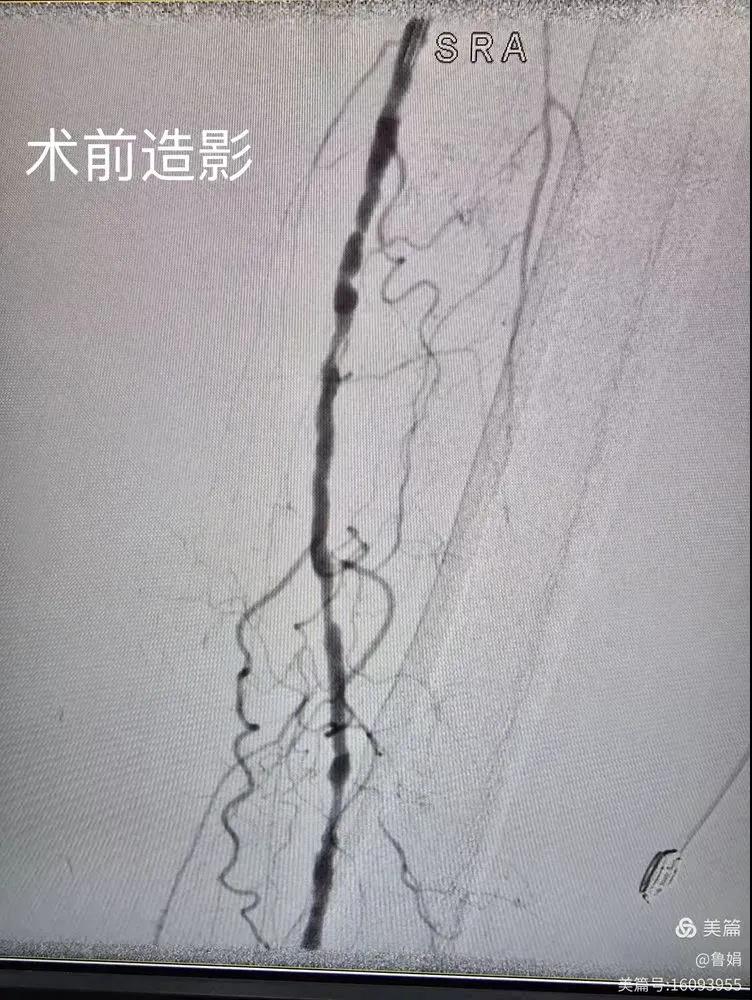

據(jù)悉,該患者,女,73歲,下肢動脈硬化閉塞癥,“以靜息痛,間歇性跛行”入院,CTA評估:股淺動脈,腘動脈間斷性多段重度狹窄,外二科血管外科團隊根據(jù)患者病情,結(jié)合檢查結(jié)果,經(jīng)過科室會診后,決定對該病人行介入治療。手術(shù)由周創(chuàng)業(yè)副主任與北大一院血管外科專家郭宏杰教授聯(lián)合開展,對股淺動脈,腘動脈重度閉塞段行血管開通+藥涂球囊擴張成形,術(shù)后狹窄明顯緩解,血流恢復!